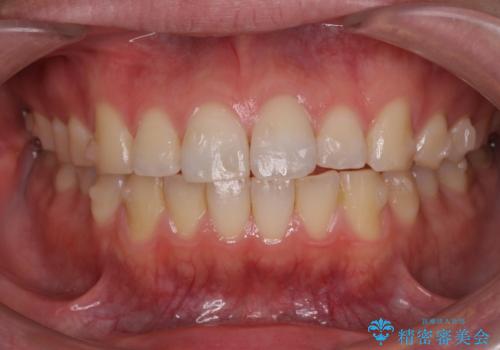

前歯が気になる。インビザラインライト

- 前歯が気になるとの事で来院。

矯正を希望されたが費用と時間を抑えたいとの事でインビザラインライトで矯正を行いました。(奥歯の位置関係はほぼ変えない)

前歯が綺麗に並び大変満足して頂けました。